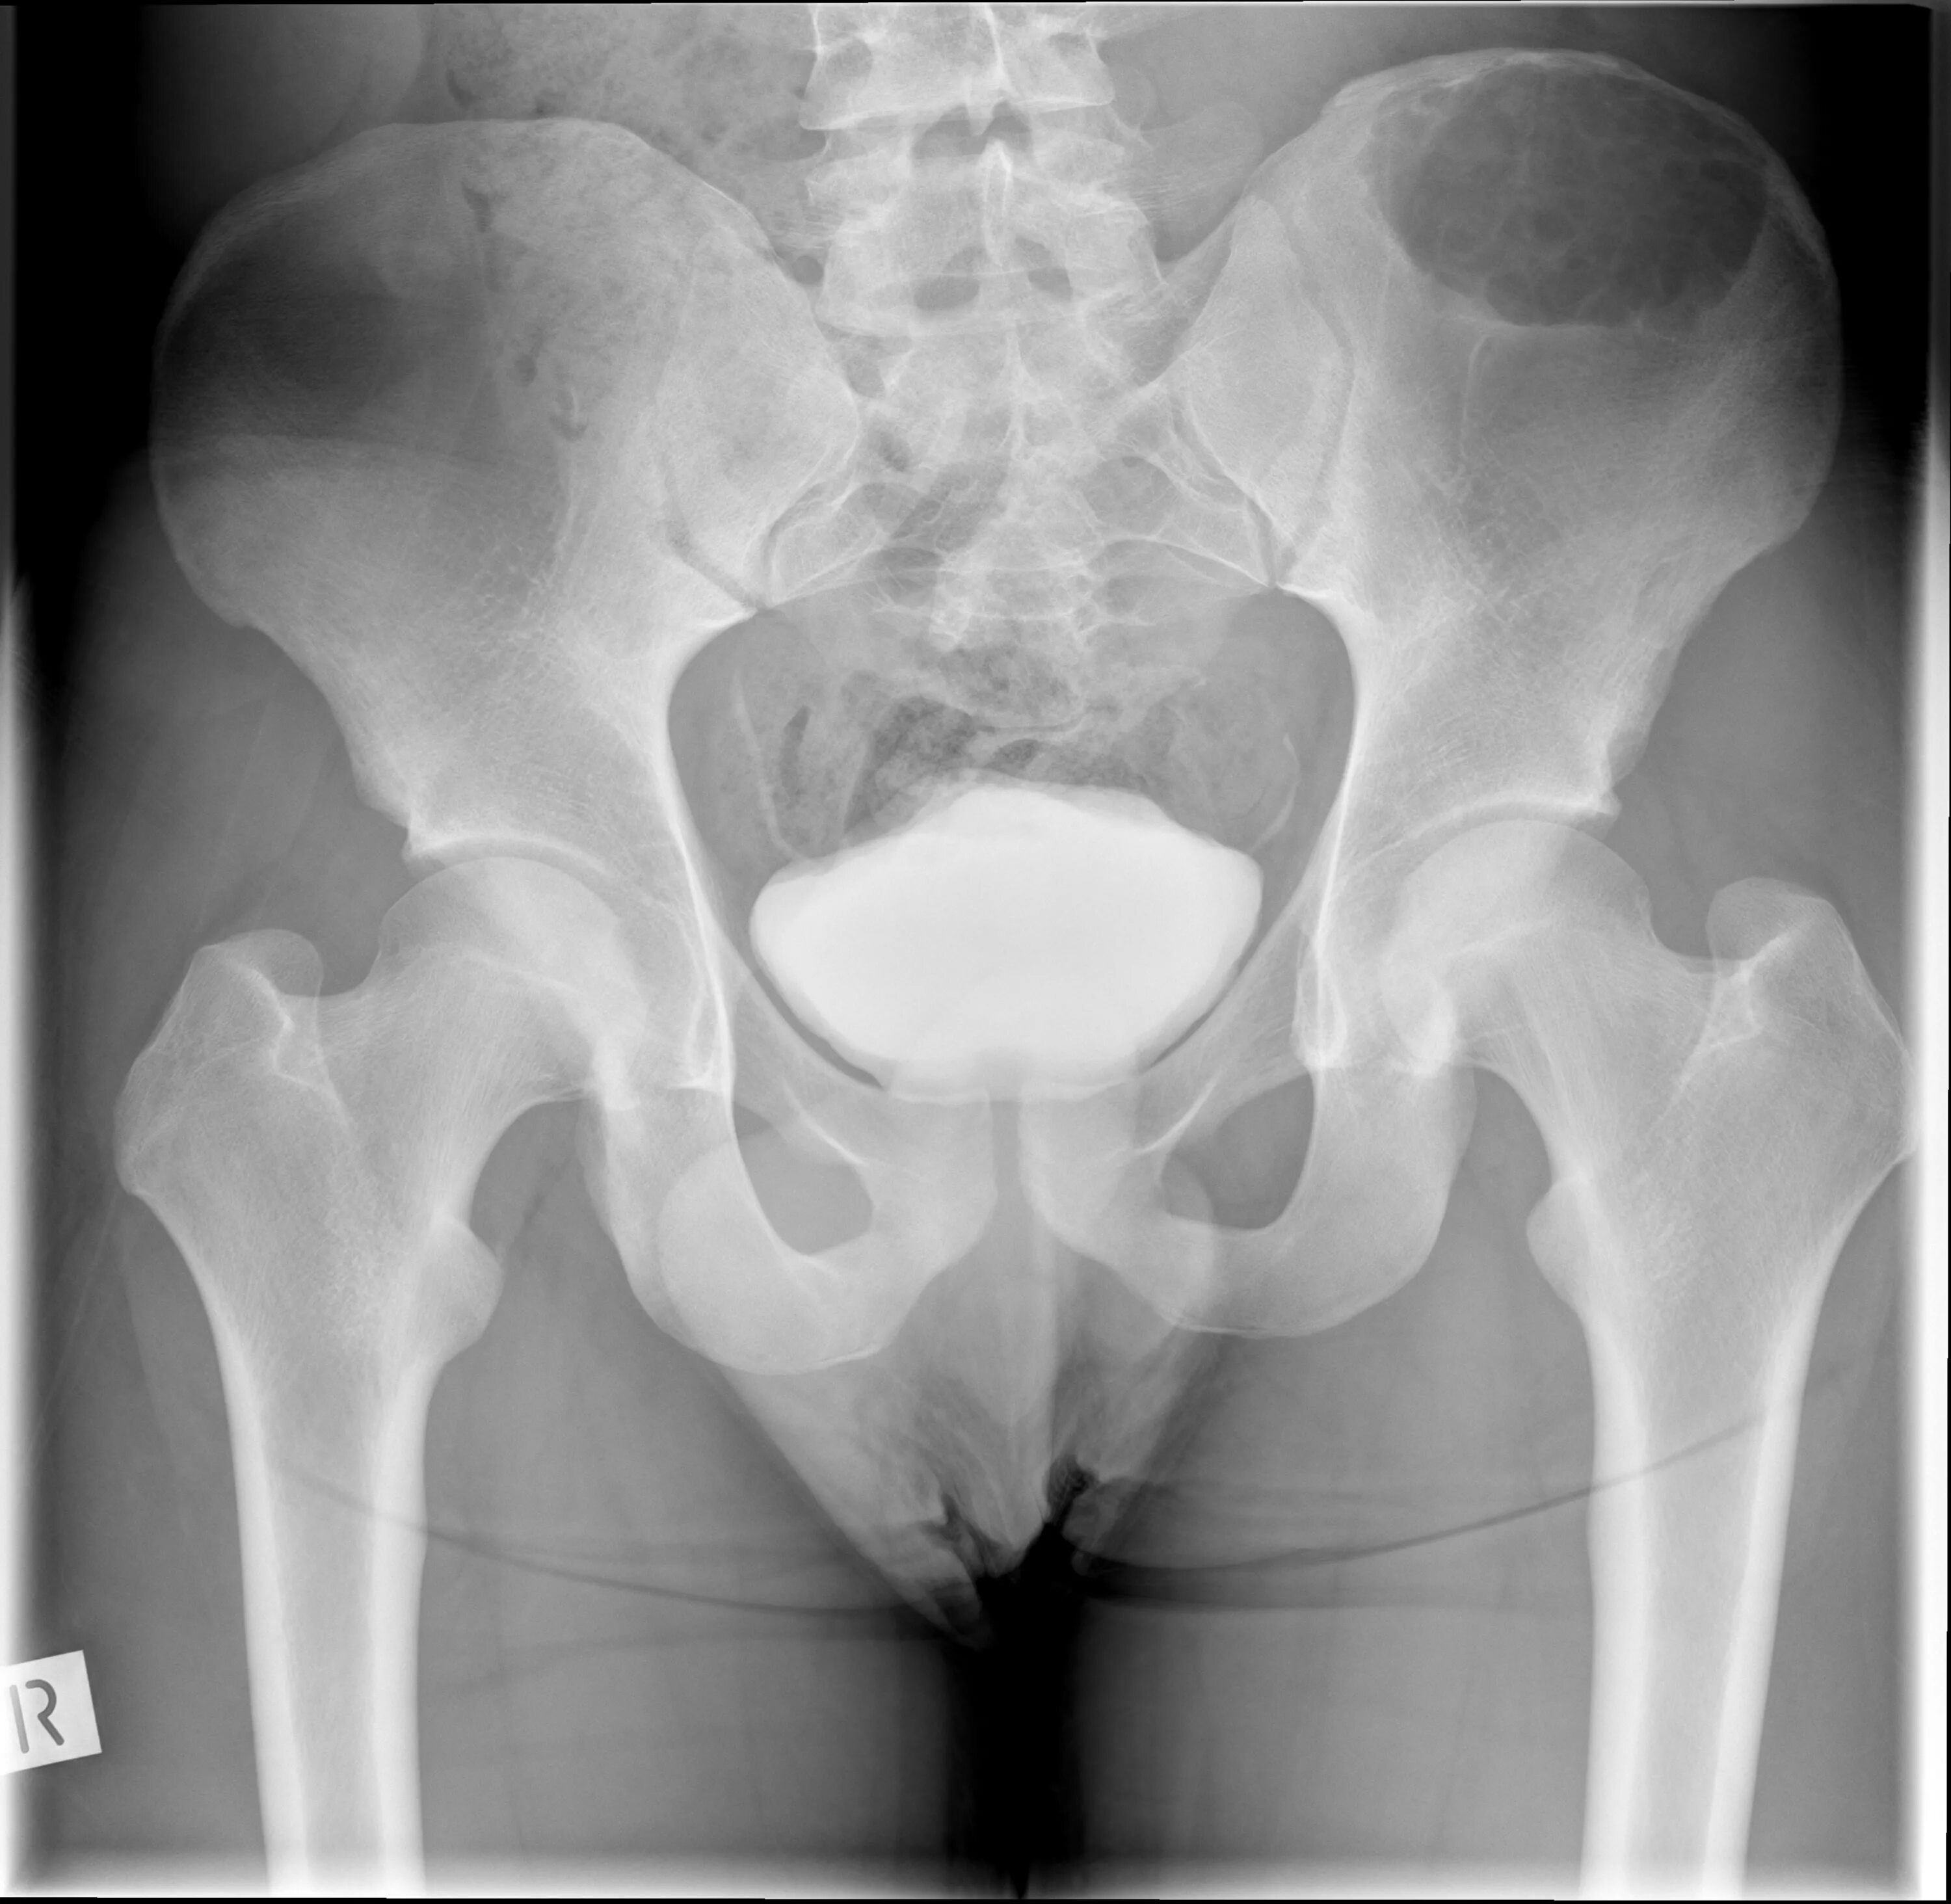

Метастазы в тазобедренном